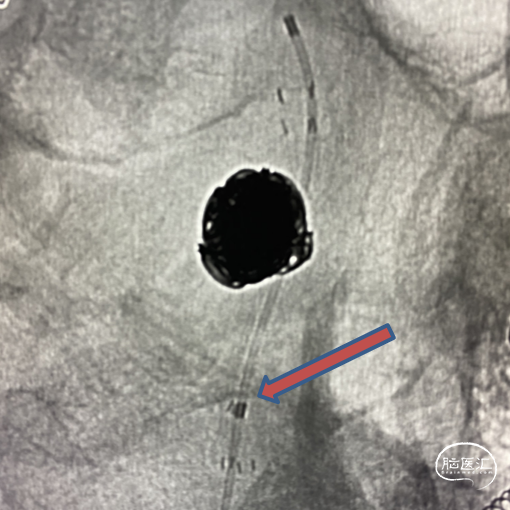

弹簧圈部分释放,植入Enterprise 4.5mm×28mm覆盖责任动脉瘤瘤颈,后填塞弹簧圈,支架保护载瘤动脉欠佳。

给予部分回收弹簧圈,赛诺Neuro LPS™颅内低压球囊到位支架内,命名压力充盈球囊保持支架稳定性,防止支架塌陷保护载瘤动脉。

重复上述过程,继续送入6枚弹簧圈,造影显示动脉瘤栓塞完全载瘤动脉通畅。

为减少复发概率给予第二枚EP支架叠加。

载瘤动脉近端支架覆盖处狭窄,给予赛诺Neuro LPS™颅内低压球囊后扩。